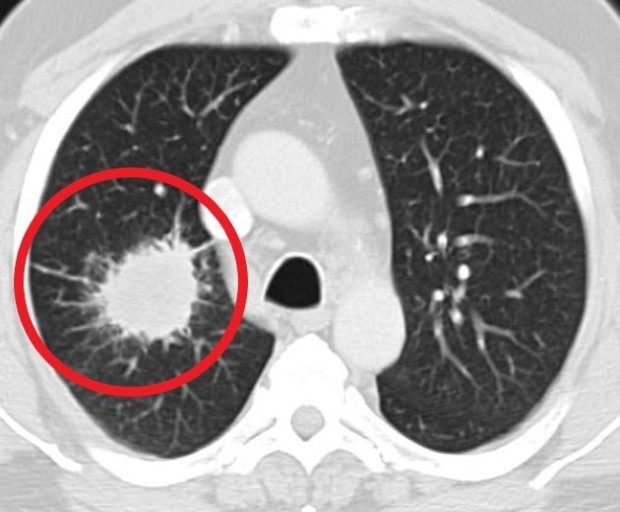

안녕하세요! 오늘은 폐렴의 초기 증상에 대해 알아보려고 합니다. 갑자기 기침이 심해지거나 숨이 차는 등 평소와 다른 호흡의 변화가 있을 때, 그 증상이 단순한 감기인지 아니면 폐렴으로 이어지는 문제인지를 구분하는 것이 중요합니다. 폐렴은 빠르게 진행될 수 있기 때문에, 초기 증상에 대한 인식을 높이는 것이 예방과 치료에 큰 도움이 됩니다.

폐렴은 조기에 치료하면 완치가 가능하지만, 늦으면 합병증이 발생할 수 있으므로 증상이 나타나면 즉시 의료기관을 방문하는 것이 중요합니다.

폐렴의 초기 증상을 잘 알고 있다면, 더 빠르게 적절한 조치를 취할 수 있습니다. 만약 자신이나 주변에 폐렴 의심 증상이 나타난다면, 지체하지 말고 병원을 방문해 꼭 진료를 받으세요. 건강은 무엇보다 중요하니까요! 이번 글이 도움이 되셨기를 바랍니다. 감사합니다.